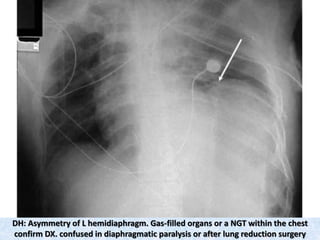

DH: Asymmetry of L hemidiaphragm. Gas-filled organs or a NGT within the chest

confirm DX. confused in diaphragmatic paralysis or after lung reduction surgery

DH: Asymmetry ofL hemidiaphragm. Gas-filled organs or a NGT within the chest confirm DX. confused in diaphragmatic paralysis or after lung reduction surgery